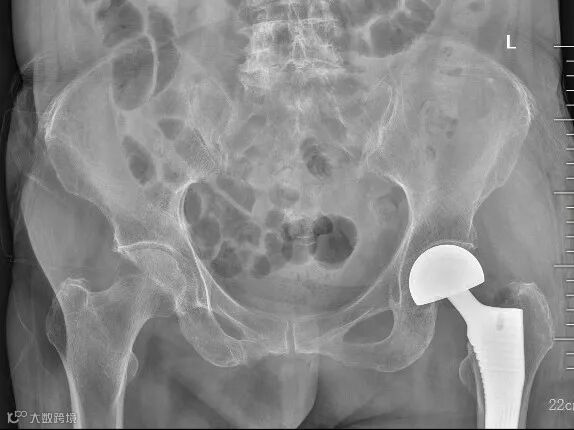

第二术前影像资料